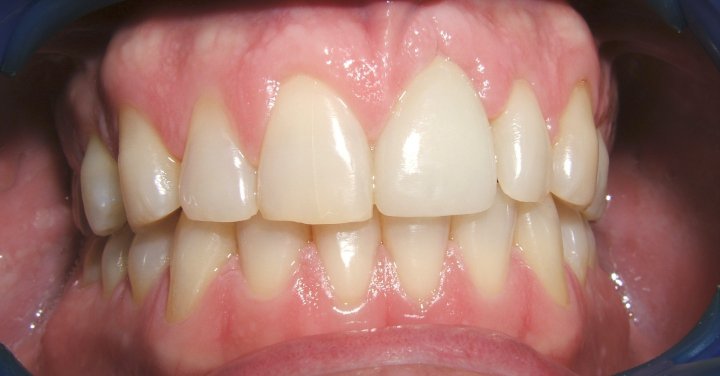

Final

Procera Full Porcelain Crown In The Implant